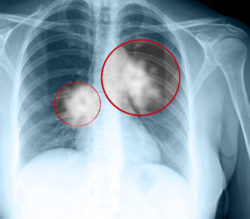

Mesothelioma is a very rare form of lung cancer specifically caused by asbestos exposure. It attacks the membrane that lines the outside of the lungs. This disease is oftentimes diagnosed at a late stage, due to the mesothelioma latency period.

The fibers can become embedded in either the lungs or stomach, and may eventually fester into cancer cells. In the past few years, reports of asbestos exposure injuries had significantly increased due to the number of veterans and retired laborers being exposed to asbestos when they were younger.